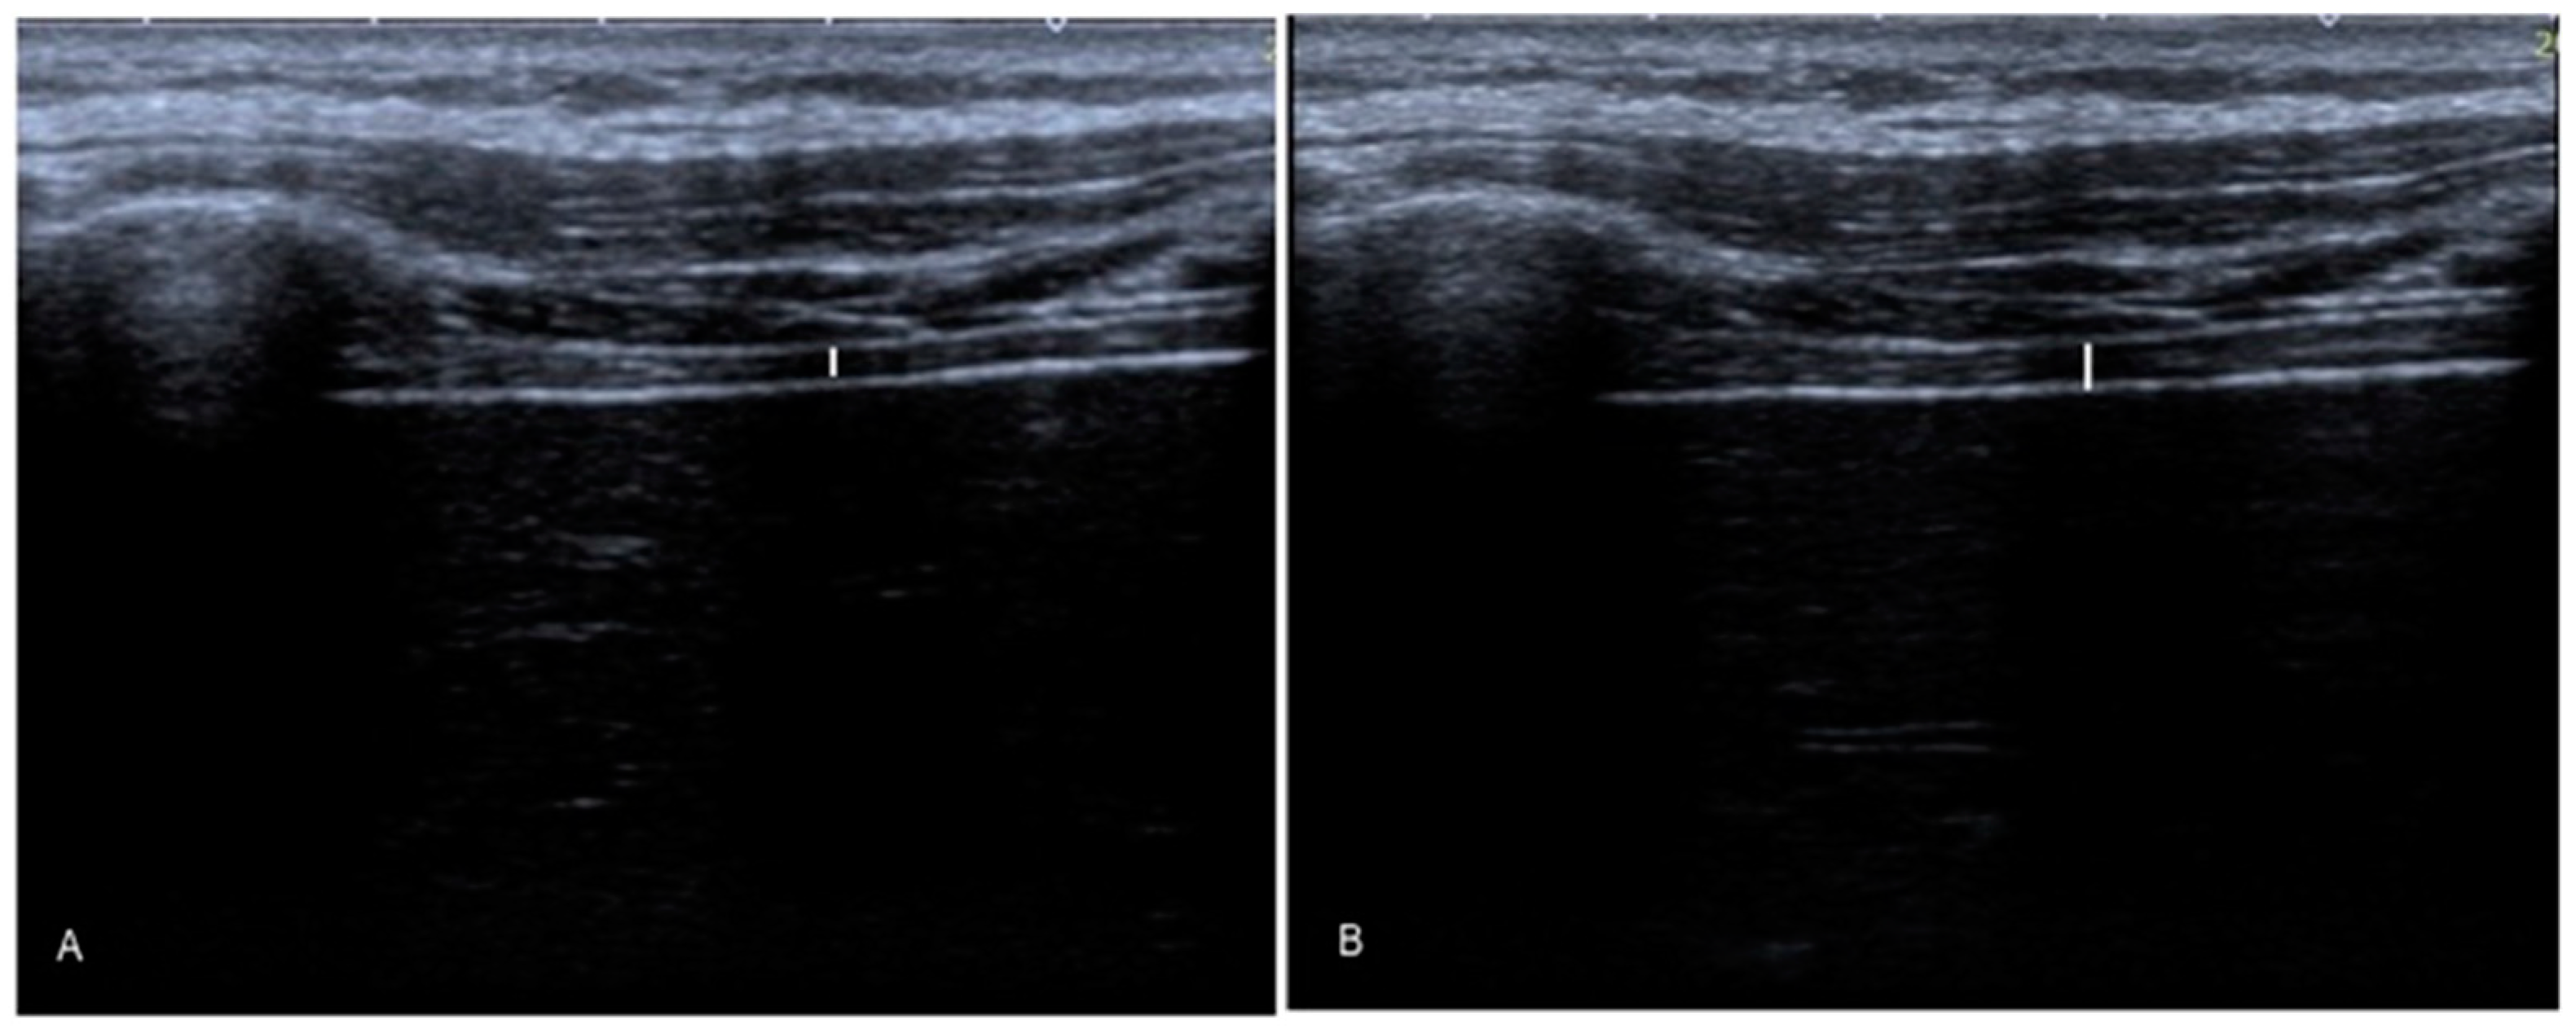

2.5.1. Diaphragm Thickness

- Goligher, E.C.; Laghi, F.; Detsky, M.E.; Farias, P.; Murray, A.; Brace, D.; Brochard, L.J.; Sebastien-Bolz, S.; Rubenfeld, G.D.; Kavanagh, B.P.; et al. Measuring diaphragm thickness with ultrasound in mechanically ventilated patients: Feasibility, reproducibility and validity. Intensive Care Med. 2015, 41, 642–649. [Google Scholar] [CrossRef]

- Calvo-Lobo, C.; Almazán-Polo, J.; Becerro-de-Bengoa-Vallejo, R.; Losa-Iglesias, M.E.; Palomo-López, P.; Rodríguez-Sanz, D.; López-López, D. Ultrasonography comparison of diaphragm thickness and excursion between athletes with and without lumbopelvic pain. Phys. Ther. Sport 2019, 37, 128–137. [Google Scholar] [CrossRef]